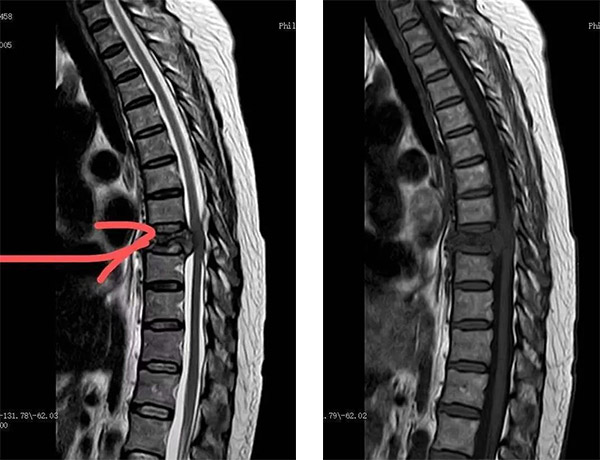

胸8椎体病理性骨折,溶骨性破坏

胸8水平脊髓受压